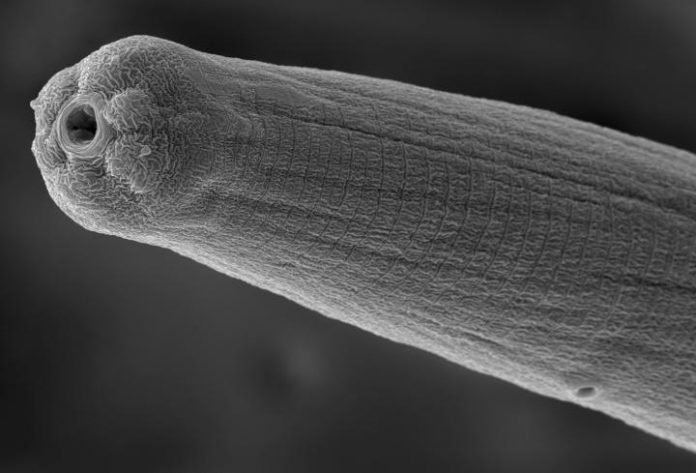

By some estimates, nearly a quarter of the world’s population is infected with various types of microscopic worms, or nematodes, with effects ranging from cognitive impairment and blindness to debilitation, elephantiasis, and death.

“You can have a person riddled with infection who never realized there’s a 2-centimeter-long worm in their eye and thousands of parasites in their blood,” Dillman said. “The immune system never signaled something was wrong. How is that possible? We know very little about how that works.”

Dillman is focused specifically on the proteins that nematode spit releases into hosts during an infection.

Scientists know the venom alters the immune system of a host and somehow helps the worms avoid detection. However, there are hundreds of proteins released in nematode venom during an infection, and only about 10 have been characterized and understood.